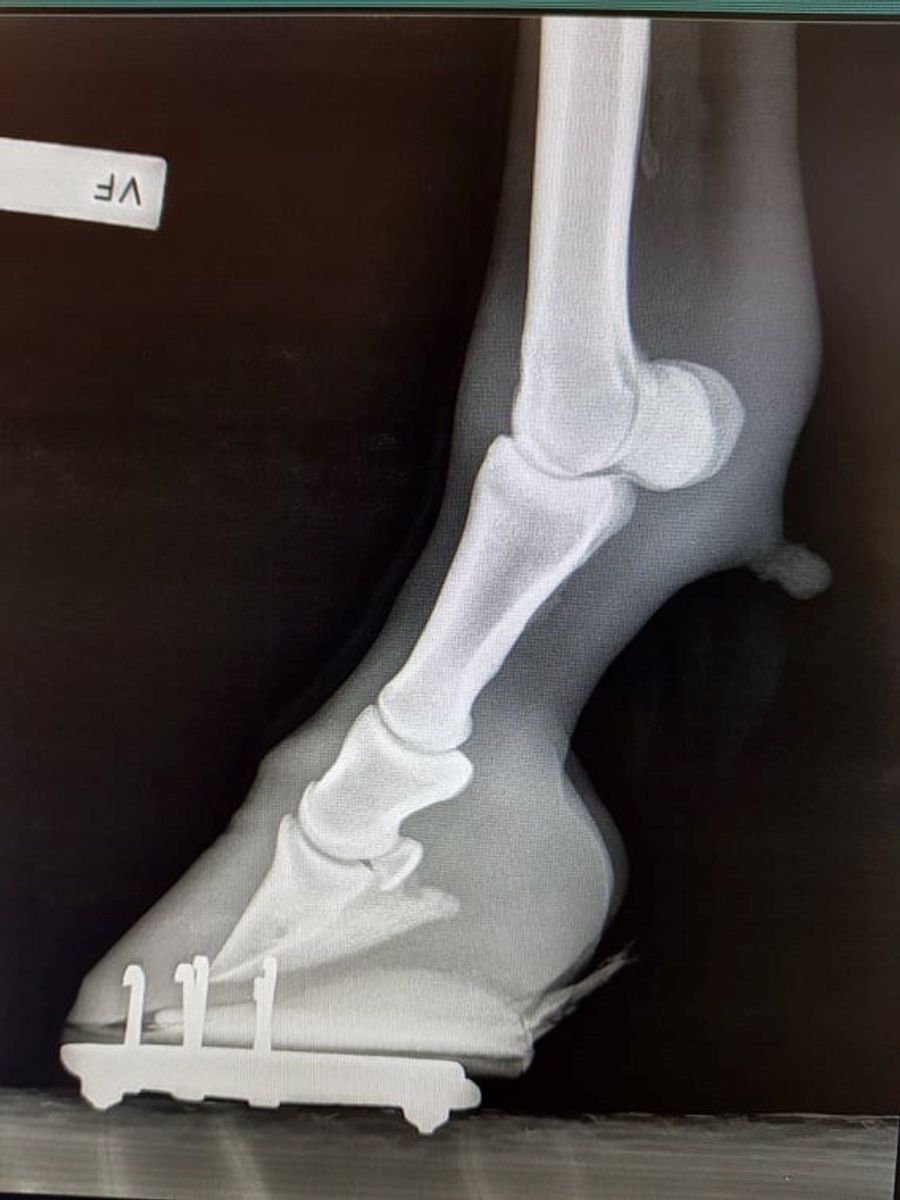

Hester med EMS vil ofte utvikle forfangenhet som følge av de forhøyede insulinnivåene. Forfangenhet er en smertefull sykdomstilstand i høvene som i verste fall kan ende i avlivning av dyrevelferdshensyn.